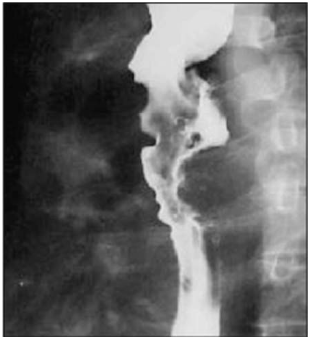

Um paciente de 62 anos de idade, tabagista (1maço/dia) e etilista (5 doses de destilado/dia) há 40 anos, procurou atendimento ambulatorial com queixa de disfagia progressiva (sólidos para líquidos), linfonodomegalia cervical bilateral e perda de 8 kg em seis meses. Foi submetido a estudo contrastado do esôfago, que demonstrou falha de enchimento irregular.

No que se refere ao caso clínico citado, a localização mais comum dessa patologia é

Disponível em: <www.rb.org.br>. Acesso em: 16 fev. 2023.

Diante dessas informações, qual é a principal hipótese diagnóstica?